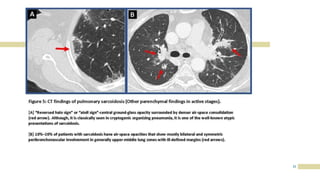

CHEST X RAY

IN

SARCOIDOSIS

17

18